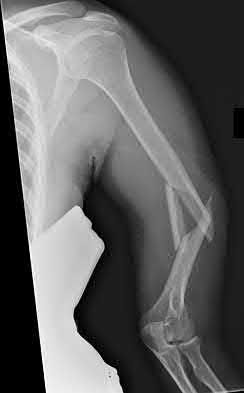

1035) Figures 188a and 188b are the radiographs of a 6' 1" 205-lb 22-year-old female collegiate basketball player who landed awkwardly on her right leg during practice and collapsed on the ground. She immediately reported severe pain in her right leg and could not move her right knee. Examination in the emergency department reveals symmetric dorsalis pedis and posterior tibial pulses in her lower extremities. An MRI scan reveals anterior cruciate ligament, posterior

cruciate ligament, and posterolateral corner injury. What is the next most appropriate step in management?

Corrent answer: 4

Management should include emergent closed reduction and observation overnight for neurovascular compromise and compartment syndrome. The radiographs clearly show an anterior knee dislocation. This condition can result in vascular and/or neurologic compromise and represents a true emergency.

Initial treatment is emergent closed reduction followed by close observation for 24 to 48 hours. Some controversy exists regarding the indications for invasive vascular studies out of concern for occult catastrophic arterial injury. Stannard

and associates and Klineberg and associates studied the incidence of vascular compromise following knee dislocation and concluded that patients with symmetric lower extremity pulses were at low risk for progression to vascular compromise. As a result, selective arteriography based on serial physical examinations is a safe and prudent policy following knee dislocation. Definitive treatment of the ligamentous injuries is not advocated in the immediate period following injury because of the need to ensure the vascular integrity of the limb. Repair versus reconstruction of damaged ligaments at a later time is controversial, with some authors advocating early repair/reconstruction while others support reconstruction in a staged fashion.